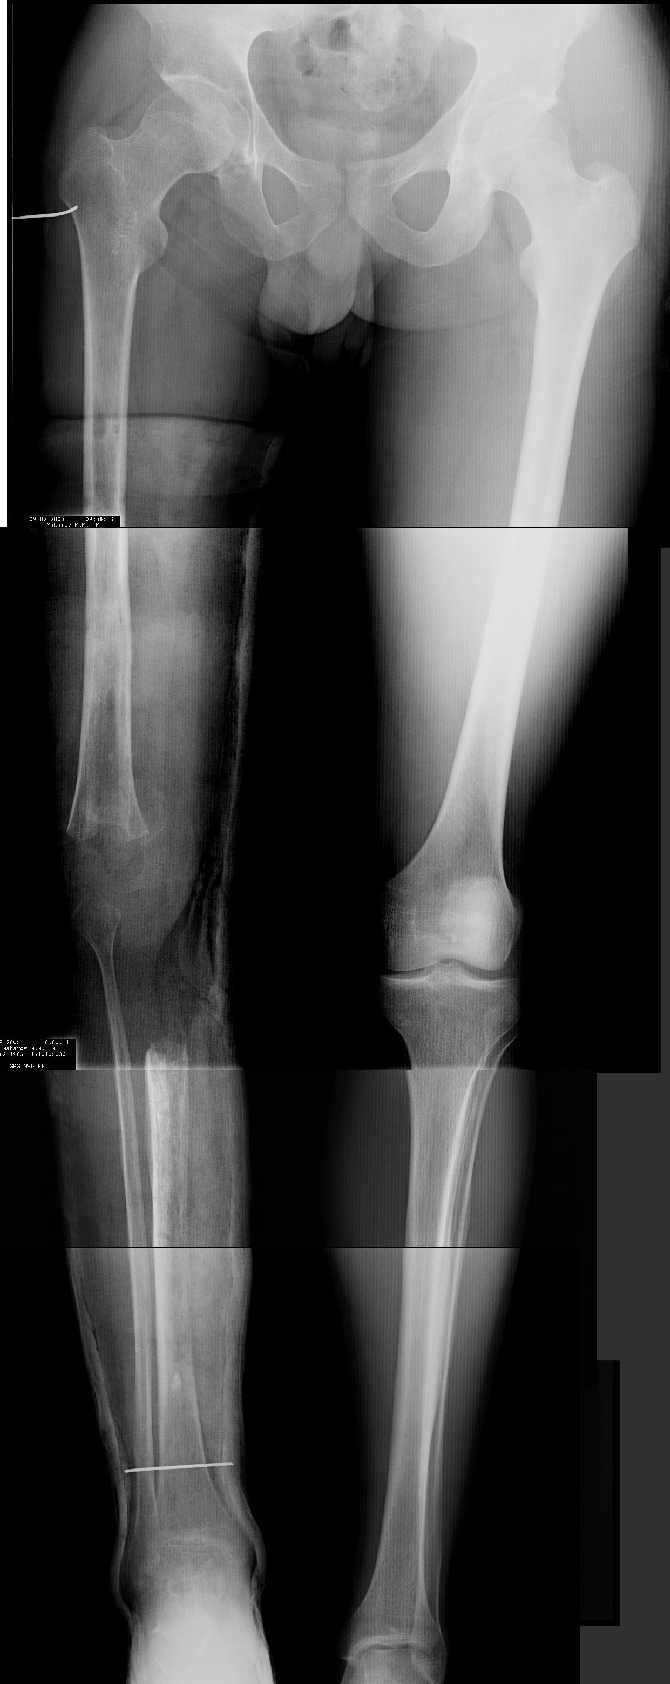

Прежде всего необходимо выполнить рентгенографию в таком положении, как это показано на рис.

После этого представится возможность оценить ось и сравнитьеё с нормой Рисунки из кники Dror Paley - Принципы коррекции деформаций. Этой теме посвящены 800 страниц. Хотя, учитывая контрактуру, это исследование не будет исчерпывающим.

AV> многооскольчатый перелом правой бедреннойљ кости на границе

AV> средней и нижней трети со смещением,

AV> В настоящее время стойкая разгибательная контрактура правого

AV> коленного сустава (сгибание 105-110 гр., разгибание 160-165 гр.),

AV> варусная деформация, болевой синдром.

имеется S-образная деформация бедра на фоне "многооскольчатого

перелома правой бедреннойљ кости на границе средней и нижней трети со смещением"

(хотя "длинные" снимки конечно же не помешали бы...)

На представленных снимках эта деформация как раз и не представлена.

1. Иллюстрации - во вложении.

Два бедра после эндопротезирования.

Авторы операции долго думали почему больная хромает.

Сдклали снимок - одна нога короче почти на 3 см.

Здоровый человек и то будет хромать.

2. Другой пример - дефект после инфицирования коленного эндопротеза.

Предполагалось, что величина дефекта 11-12 см. Так получается, если

сделать снимок только области коленных суставов. Определить

укорочение сложно, так как нога просто болтатется.

Сделали снимок "от и до" - величина дефекта 17 см.